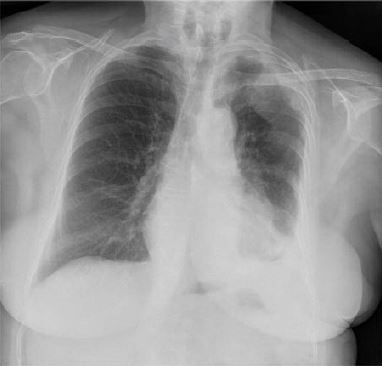

El mesotelioma maligno es una neoplasia que se origina de las células mesoteliales de la pleura, pericardio, cavidad peritoneal y túnica vaginalis. Revisamos los casos en nuestra población de mesotelioma pleural desde 2007.